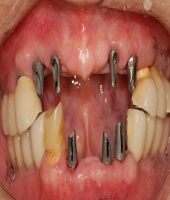

| ● 진료과목 : [임플란트] 어테치먼트를 이용한 틀니치료

| ● 내용 : 오래된 틀니 사용으로, 골흡수가 심하게 진행된 고령의 무 |